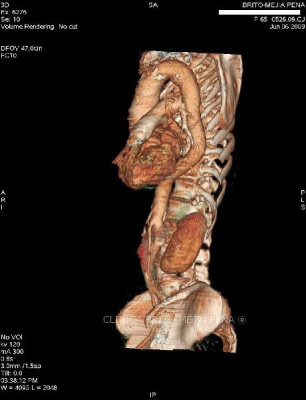

Cuerpo extraño en bronquio derecho 3D